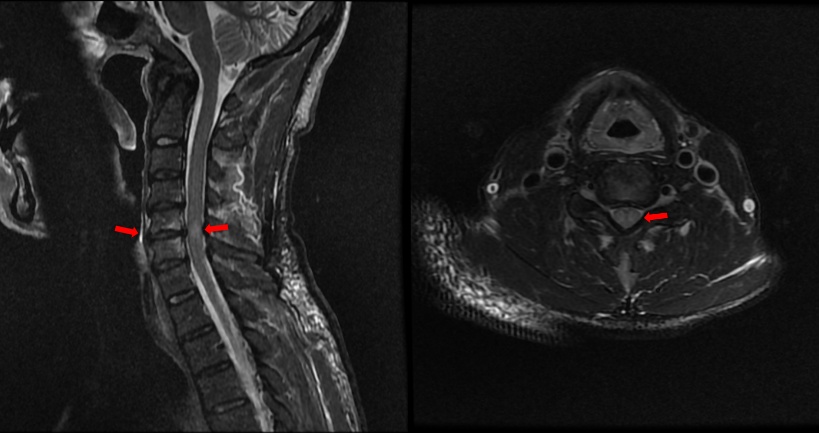

患者第二天醒酒后诉症状未见好转,外一科医生立即发起了紧急会诊。我院援滇医疗专家医师徐委参与了会诊,查体发现患者额面部伤口,颈椎有压痛,双上肢痛觉过敏,双手肿胀明显,握力仅有1级,双下肢行走不稳,患者上肢已几近瘫痪,生活完全无法自理。经过症状、体征的全面检查,徐医生考虑患者存在颈椎过伸伤伴颈脊髓损伤可能,建议立即完善颈椎核磁共振(MRI)检查。

检查结果印证了徐医生的判断,患者颈5/6椎间盘水平脊髓已经出现了信号异常,表明已经存在颈脊髓损伤。结合患者的病史、症状、体征及影像学检查,考虑患者为颈椎过伸伤伴颈脊髓损伤,AIS B级,依据同济医院脊柱外科学科带头人程黎明教授撰写的《过伸性颈脊髓损伤诊疗临床循证指南》,该患者伴有椎间盘韧带复合体(Disco-Ligamentous Complex, DLC)损伤,属于程氏分型C3型,亟需尽早手术解除压迫,挽救受损的神经。